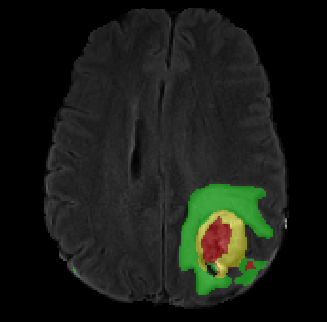

Data augmentation has been widely used for training deep learning systems for medical image segmentation and plays an important role in obtaining robust and transformation-invariant predictions. However, it has seldom been used at test time for segmentation and not been formulated in a consistent mathematical framework. In this paper, we first propose a theoretical formulation of test-time augmentation for deep learning in image recognition, where the prediction is obtained through estimating its expectation by Monte Carlo simulation with prior distributions of parameters in an image acquisition model that involves image transformations and noise. We then propose a novel uncertainty estimation method based on the formulated test-time augmentation. Experiments with segmentation of fetal brains and brain tumors from 2D and 3D Magnetic Resonance Images (MRI) showed that 1) our test-time augmentation outperforms a single-prediction baseline and dropout-based multiple predictions, and 2) it provides a better uncertainty estimation than calculating the model-based uncertainty alone and helps to reduce overconfident incorrect predictions.

翻译:数据增强被广泛用于培训医学图像分化的深层学习系统,在获得稳健和转化变异预测方面发挥重要作用,但很少在测试时用于分解,也没有在一致的数学框架内制定。在本文中,我们首先提出为在图像识别方面深层学习而进行测试-时间增强的理论性表述,通过蒙特卡洛模拟估计其预期值和图象获取模型中先前的参数分布,涉及图像转换和噪音。然后,我们根据已制定的测试-时间增强,提出新的不确定性估计方法。2D和3D磁共振图像对胎儿大脑和脑肿瘤的分解实验表明,1)我们的测试-时间增强超过单位基线和基于辍学的多重预测,2)它比仅仅计算基于模型的不确定性和帮助减少过分自信的不正确预测,提供了更好的不确定性估计。